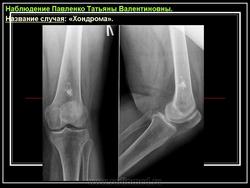

Рентгенологическая картина хондромы представляет четко очерченный опухолевый узел. Очаги минерализации в хондромах выглядят достаточно характерно и представлены очаговыми, глыбчатыми или кольцевидными , арочными отложениями извести. Полного разрушения кортикального слоя трубчатой кости с выходом опухолевых масс в мягкие ткани не наблюдается.